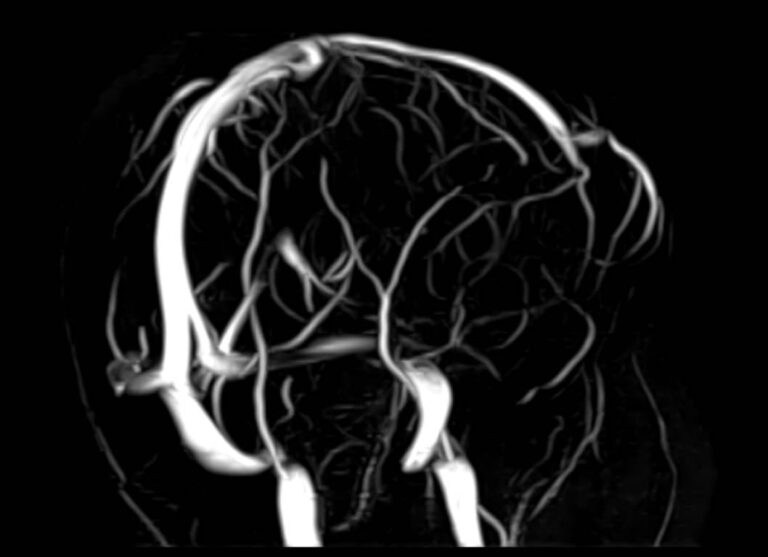

Стандартная МРТ головного мозга дает важную информацию о состоянии и структуре мозговой ткани для выявления большого числа заболеваний, в том числе опухолевых образований, демиелинизирующих заболеваний, воспалительных процессов головного мозга и мозговых оболочек. Стандартную МРТ головного мозга дополняет МР-ангиография, которая отображает состояние артериальной системы кровоснабжения головного мозга. МР-венография головного мозга позволяет детально изучить особенности анатомического и функциональной состояния венозного русла головного мозга.

Компьютерная программа обрабатывает данные, полученные при сканировании, и формирует объемные изображения как самого мозга, так и сосудистой системы в отдельности без прилегающих тканей. Обе методики применяются одновременно и взаимодополняют друг друга, давая полную диагностическую картину.